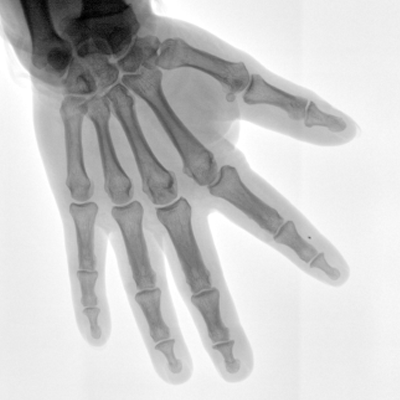

Clinical picture

臨床圖片